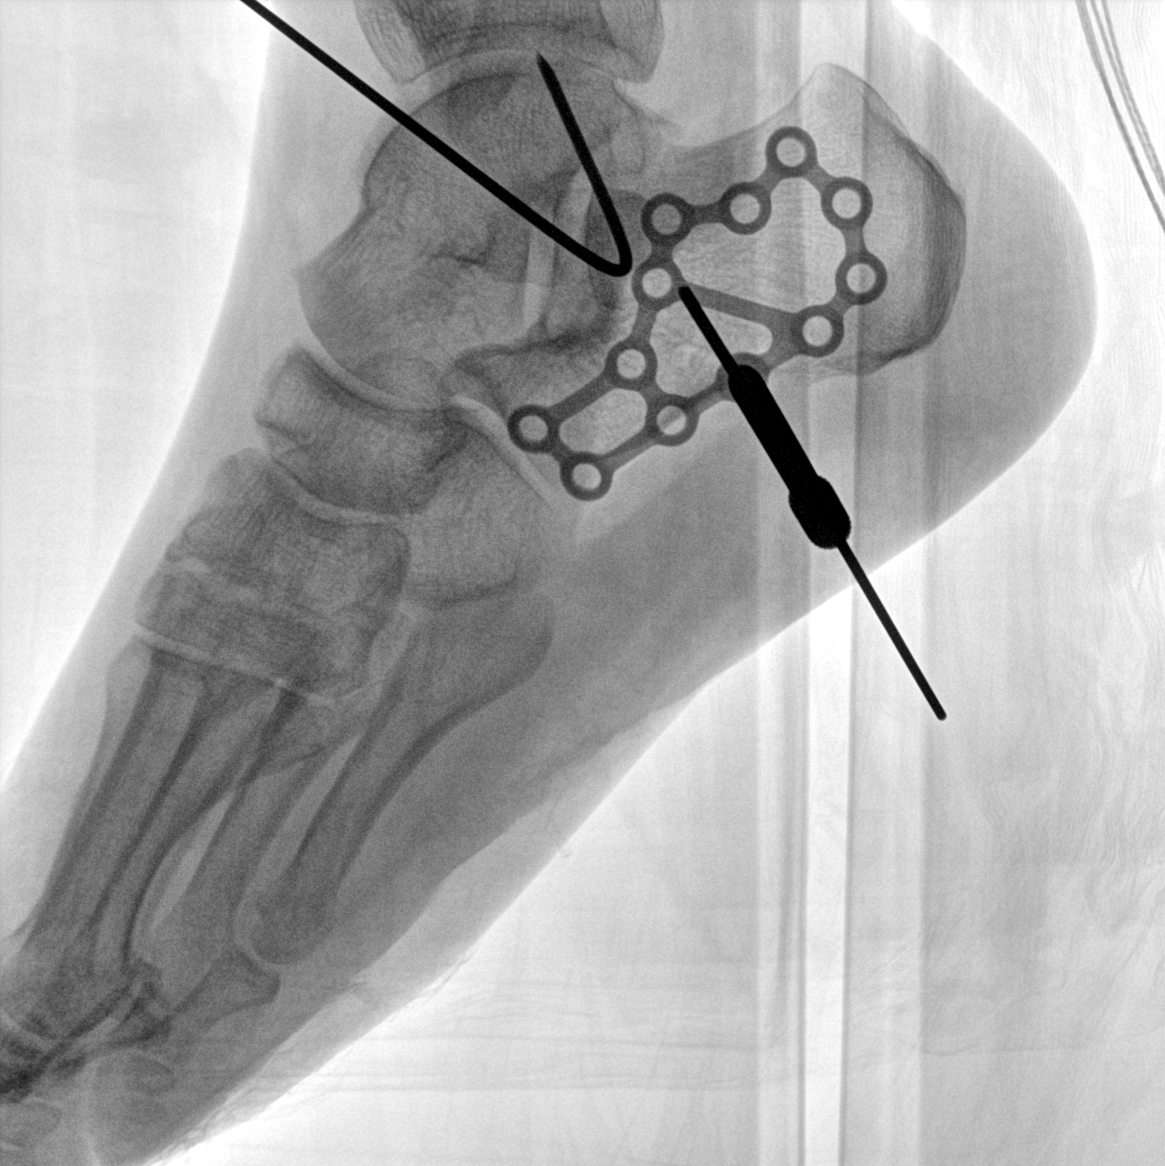

術中三維成像和橫斷面圖像提供多角度的手術診斷信息,輔助醫生進行術中評估判斷,諸如骨折復位情況和內植入螺釘的尺寸和位置,輔助手術更好地完成。